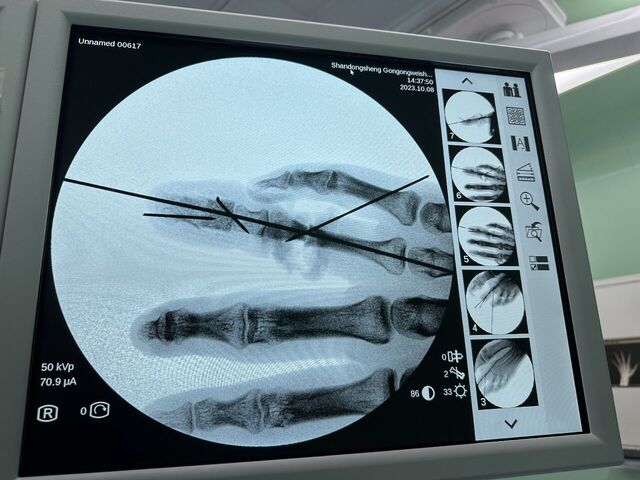

今天的环指再造

微信图片_20231008195909.jpg 微信图片_20231008195912.jpg 微信图片_20231008195906.jpg 微信图片_20231008195903.jpg 微信图片_20231008195839.jpg 微信图片_20231008195829.jpg 微信图片_20231008195945.jpg 微信图片_20231008195939.jpg